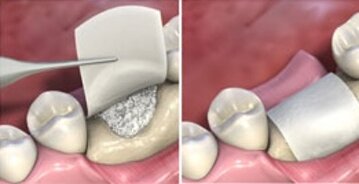

RIGENERAZIONE OSSEA GUIDATA

La Rigenerazione Ossea Guidata è una tecnica chirurgica avanzata impiegata per favorire la rigenerazione dell’osso nelle aree in cui si è verificato un riassorbimento.

Il procedimento si basa sull’utilizzo di materiali da innesto , associati a membrane, con l’obiettivo di creare un ambiente protetto e stabile che permetta la rigenerazione ossea.

Grazie a questo approccio è possibile ripristinare un volume osseo adeguato, garantendo , sia la completa integrazione dell’impianto all’interno dell’osso, sia il corretto posizionamento dello stesso, necessario per una riabilitazione protesica esteticamente armoniosa.

Le membrane di collagene evolutive

La struttura della membrana, composta da fibre di collagene dense, di elevata consistenza e resistenza, la rende una valida scelta per proteggere e stabilizzare l'innesto osseo nella maggior parte delle procedure chirurgiche.La protezione dell'innesto da batteri e contaminazione alimentare è necessaria per consentire la guarigione dei tessuti duri e molli.